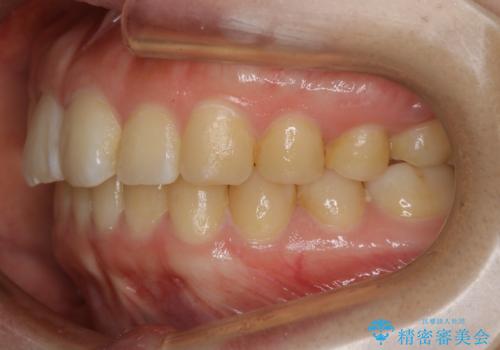

【非抜歯】ガタつきと歯軸を正して長持ちする歯へ

- 歯のガタつきと噛み合わせの改善を主訴に来院されました。

非抜歯で、少量の奥歯の移動と歯列の拡大・IPRを駆使して主訴を改善するための治療計画を立案しました。